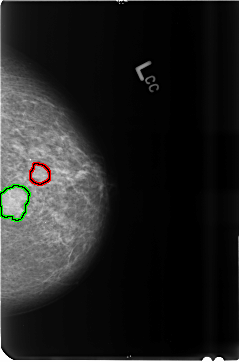

FILE: B_3515_1.LEFT_CC.OVERLAY

TOTAL_ABNORMALITIES 2

ABNORMALITY 1

LESION_TYPE MASS SHAPE ROUND-OVAL MARGINS CIRCUMSCRIBED-OBSCURED

ASSESSMENT 4

SUBTLETY 5

PATHOLOGY BENIGN

TOTAL_OUTLINES 1

BOUNDARY

ABNORMALITY 2